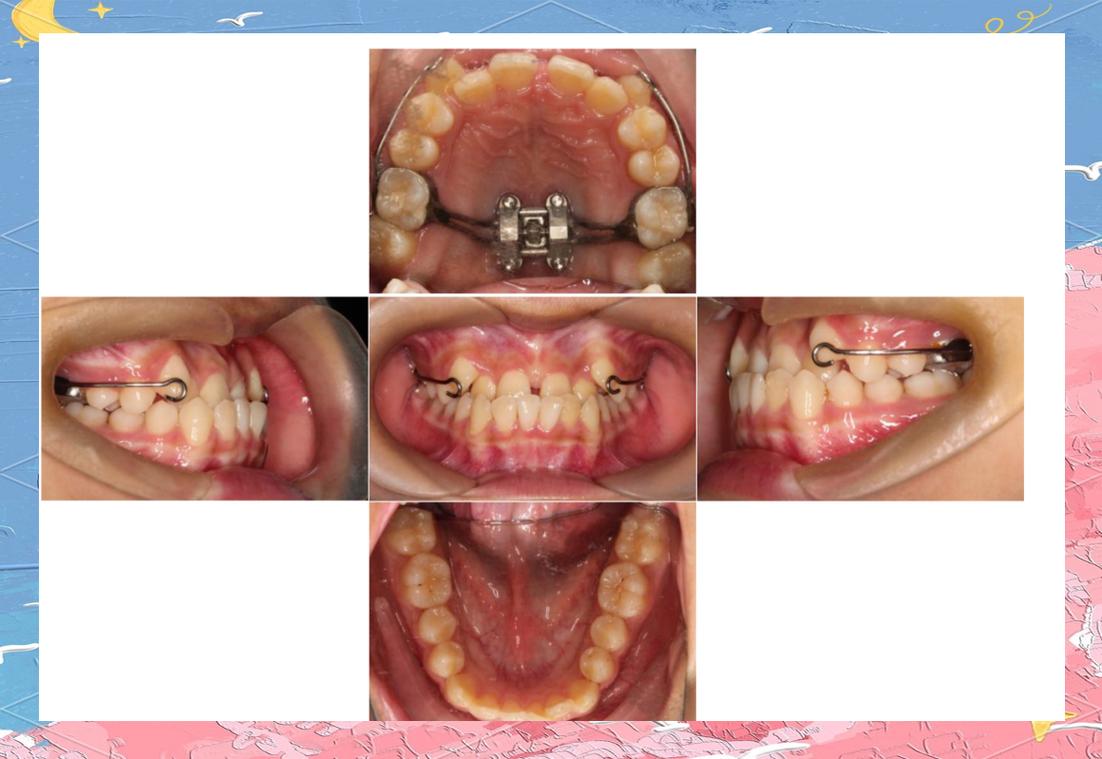

横腭杆(Transpalatal Bar,TPA)和下颌舌弓(Lingual Arch)是传统口内支抗装置,TPA通过焊接于上颌第一磨牙带环的连接杆,将两侧磨牙连成整体,限制其近中倾斜或前移,为前牙内收提供支抗,弱支抗状态下,可选用直径较细(如1.0mm)的不锈钢丝制作TPA,增加其弹性,允许磨牙轻微移动(约1-2mm),同时通过腭部软组织辅助分散力,下颌舌弓原理类似,适用于下颌磨牙支抗不足的病例,通过舌侧基托抵住前牙舌侧,防止前牙唇倾,后牙可少量前移。

Nance弓是在TPA基础上增加腭部塑料基托,利用腭穹隆黏膜与骨组织的吸附作用增强支抗,其弱支抗应用体现在:通过调整基托面积(减小基托范围)或选用弹性弓丝(如β钛丝),允许磨牙少量近中移动,同时前牙内收时,基托将部分力传递至腭部,减少后牙支抗损耗,适用于上颌前牙前突、需要少量磨牙前移的病例。